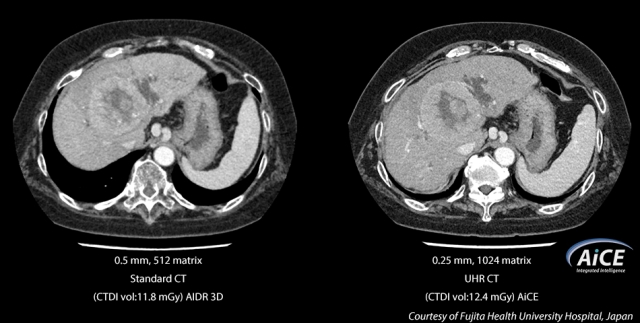

A világ első Ultra-Magas Felbontású CT (UHR CT) berendezése olyan apró anatómiai részleteket is fel tud tárni, mint például 150 mikron, olyan CT képminőséget nyújtva, amilyet általában csak katéterlaborokban látunk. Az UHR érzékelő újonnan tervezett, kétszeres felbontást biztosít a mai CT technológiákhoz képest, új érzékelővel, valamint csővel, forgótalppal és rekonstrukciós technológiákkal.

Az AiCE néven ismert mélytanuló rekonstrukciós hálózatot egy fejlett modellalapú iteratív rekonstrukciós (MBIR) algoritmuson képzik ki, hogy a mai klinikai MBIR-hez képest többszörösen gyorsabb, alacsony zajszintű, természetes textúrájú és 0,25 mm-es, 1024 mátrixú, ultranagy felbontású CT-képeket készítsen.